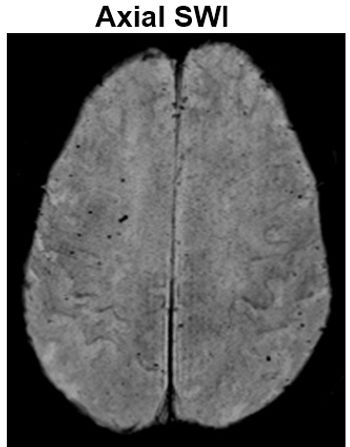

65-year-old female with sickle cell anemia and ESRD status postrenal transplant presenting with AMS and SIRS.